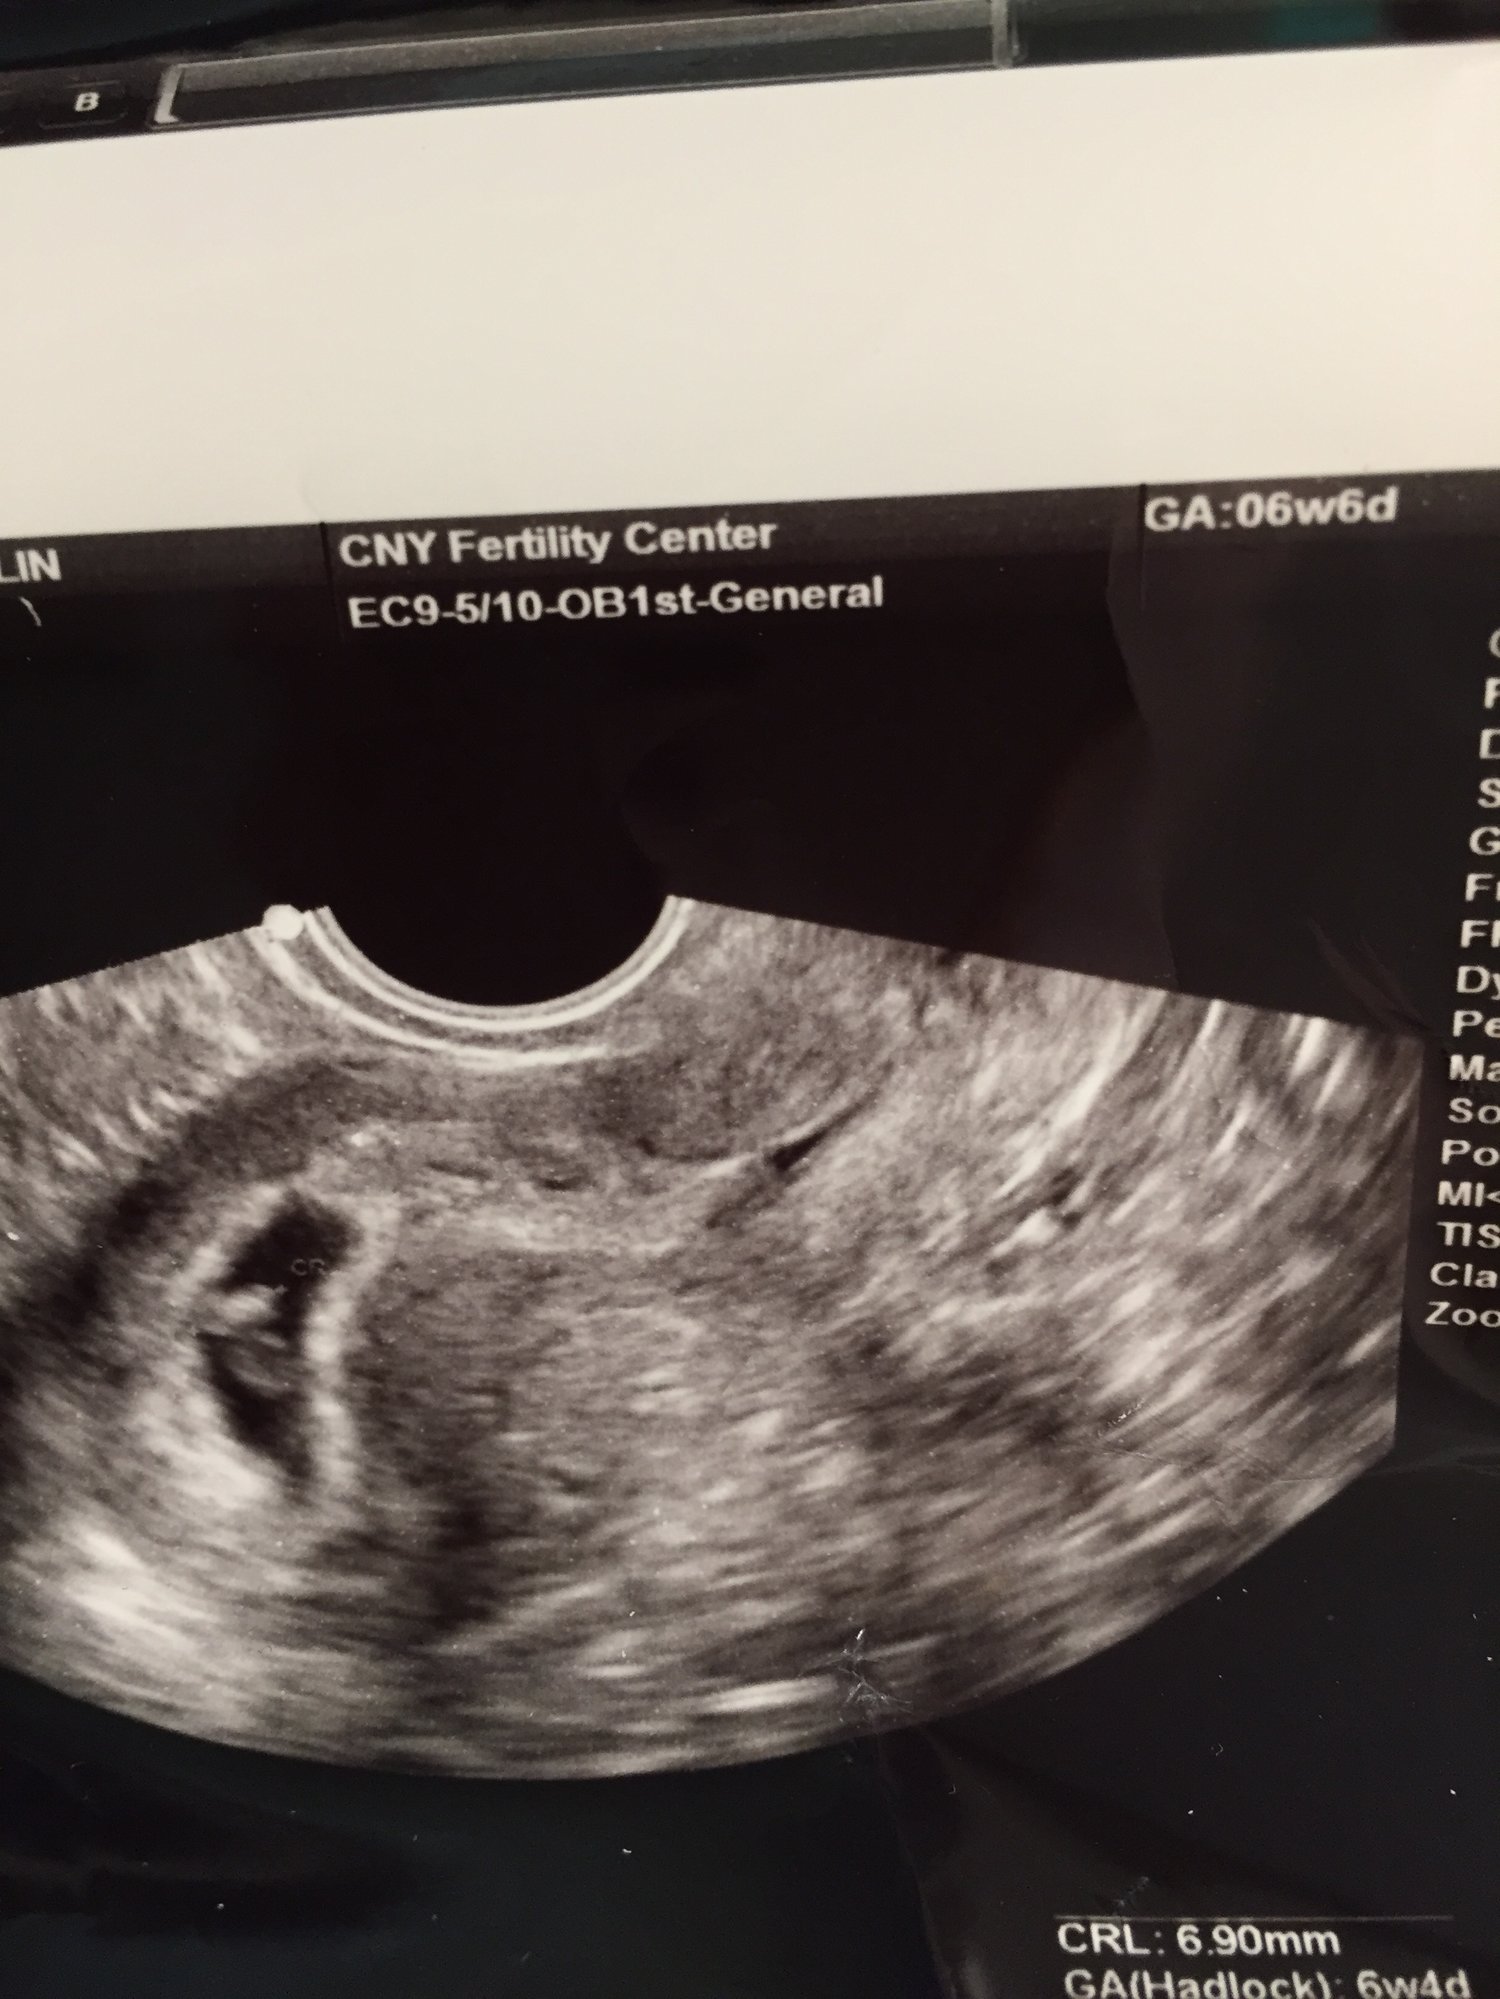

Second ultrasound today. Sweet little peanut is doing good. Heart beat strong at 150 bpm.